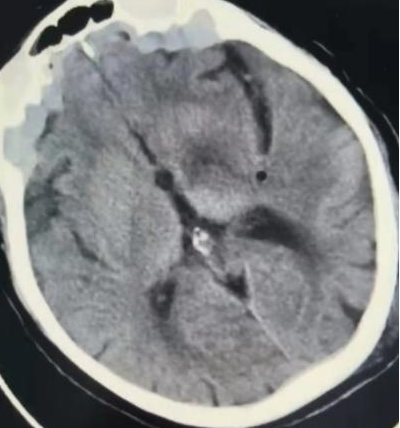

70多岁的陈老太太今年1月份出现行走不稳合并言语迟钝,就诊于我院绩溪路院区。综合多种检查结果及多科室会诊讨论意见,考虑临床诊断为B细胞淋巴瘤,华氏巨球蛋白血症的特殊表现Bing-Neel综合征可能。华氏巨球蛋白血症是淋巴瘤的一种类型,也是2023年国家公布的第二批罕见病之一,而Bing-Neel综合征又是该病尤为罕见特殊的一种临床综合征,表现为头痛眩晕、共济失调等中枢神经系统症状。患者经血液内科刘沁华医师治疗组诊治,症状逐步改善。然而,今年7月以来,患者症状再次加重,影像学检查提示颅内小脑,基底节区及颞叶多发占位。由于患者高龄,且颅内占位定性诊断困难,患者下一步的治疗方向成为困难。

病理科胡向阳主任在神经外科取得标本后马不停蹄的赶往南区,术后第二天,大体结果已出:诊断为淋巴瘤颅内侵犯,进一步分型待免疫组化结果。原来,罪魁祸首还是淋巴瘤,淋巴瘤可以有不同类型,可以累及任何一个系统,可以有各种各样的临床表现,该例陈老太太的多发颅内占位终于明确原因了。